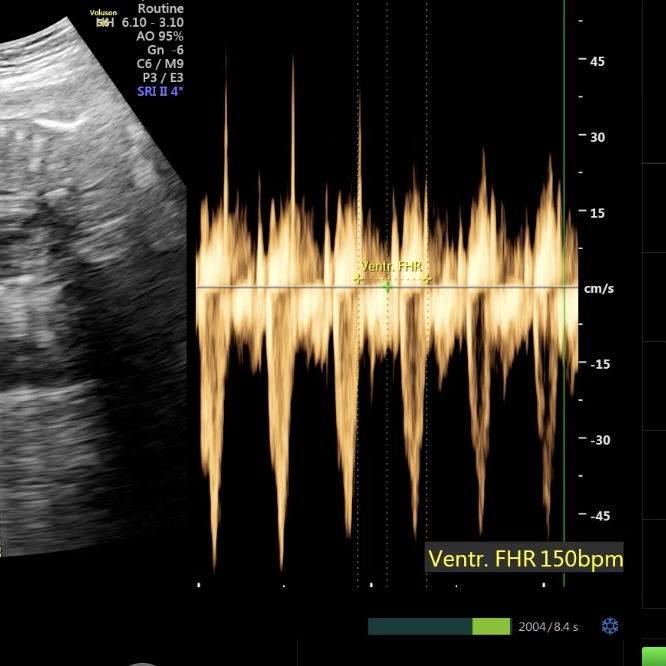

심박수는 150bpm.